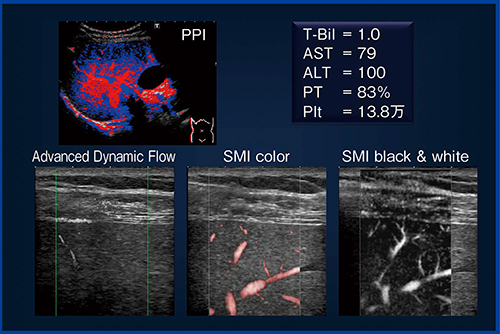

●症例1:61歳,女性,

C型慢性肝炎(F3/A2)(図4)

ADFと比べ,SMIでは血管が明瞭に描出されており,特にモノクロモードが細かい血管の描出に優れている。モノクロモードでは,バックグラウンド(Bモード)のスペックルノイズが抑制されているためと思われる。

図4 症例1:61歳,女性,C型慢性肝炎(F3/A2)